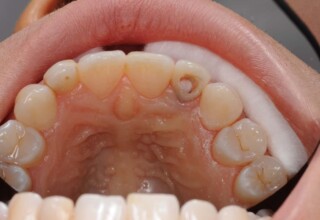

Restoration of a cracked molar with composite resin

Cracked teeth present a challenge in restorative dentistry both from the aspect of complexity of the restoration itself (usually large filings) and the necessary providings to avoid a complete fracture. The presented case demonstrates the simplest approach of a bonded direct restoration with composite resin. It is based on the principle of an adhesive filling that “holds” the remaining tooth structures “together”. The restored molar remained healthy for two years, then required a root canal and a crown was placed for maximum protection.